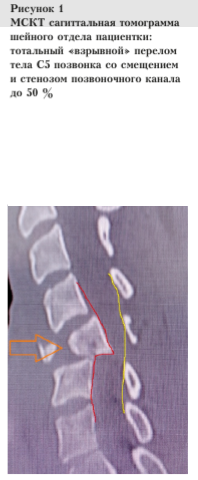

В результате проведенной мультиспиральной компьютерной томографии (МСКТ) по расширенному протоколу «политравма» (с исследованием областей: голова, шея, туловище) были получены следующие данные: травма определена как изолированная, выявлен тотальный «взрывной» перелом тела пятого шейного позвонка (С5) со смещением и стенозом позвоночного канала 50 % от его просвета (рис. 1).

На основе результатов клинического и инструментального обследования пациентке поставлен диагноз: Закрытая позвоночно-спинномозговая травма, тотальный «взрывной» перелом тела С5 позвонка со смещением, стенозом позвоночного канала до 50 %, со сдавлением и ушибом спинного мозга, нарушение проводимости по спинному мозгу с уровня С5, тетраплегия, нарушение функции тазовых органов по типу задержки, по шкале повреждений при травме спинного мозга ASIA — уровень А. Алкогольное опьянение.